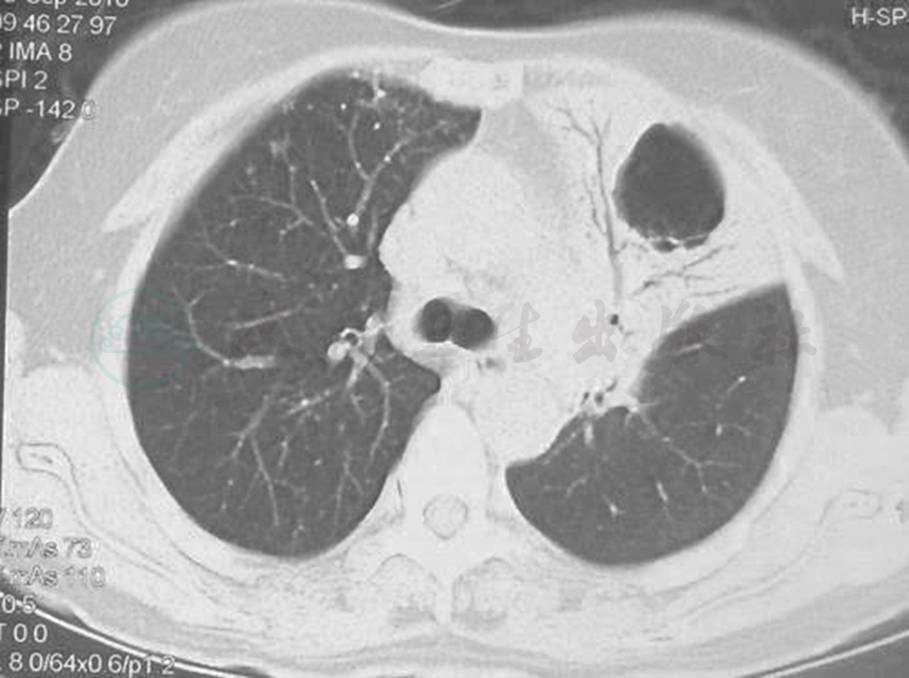

确诊后,于2010年11月25日开始予以R-CHOP方案化疗(利妥昔单抗600mg,化疗前1天;环磷酰胺0.8g,表柔比星80mg,长春地辛4mg,化疗第1天;泼尼松80mg,化疗第1~5天)。化疗3个疗程后复查胸部CT,提示肺内病变吸收不明显(图5);改为FND方案(氟达拉滨40mg,第1~3天;米托恩醌8mg,第1天;地塞米松20mg,第1~5天)化疗3个疗程,患者无明显不适主诉,胸部CT示左上肺病变较前吸收(图6)。

图5 化疗后复查胸部CT表现(2011-01)

胸部CT显示,与2010年9月比较,左肺病变无明显吸收